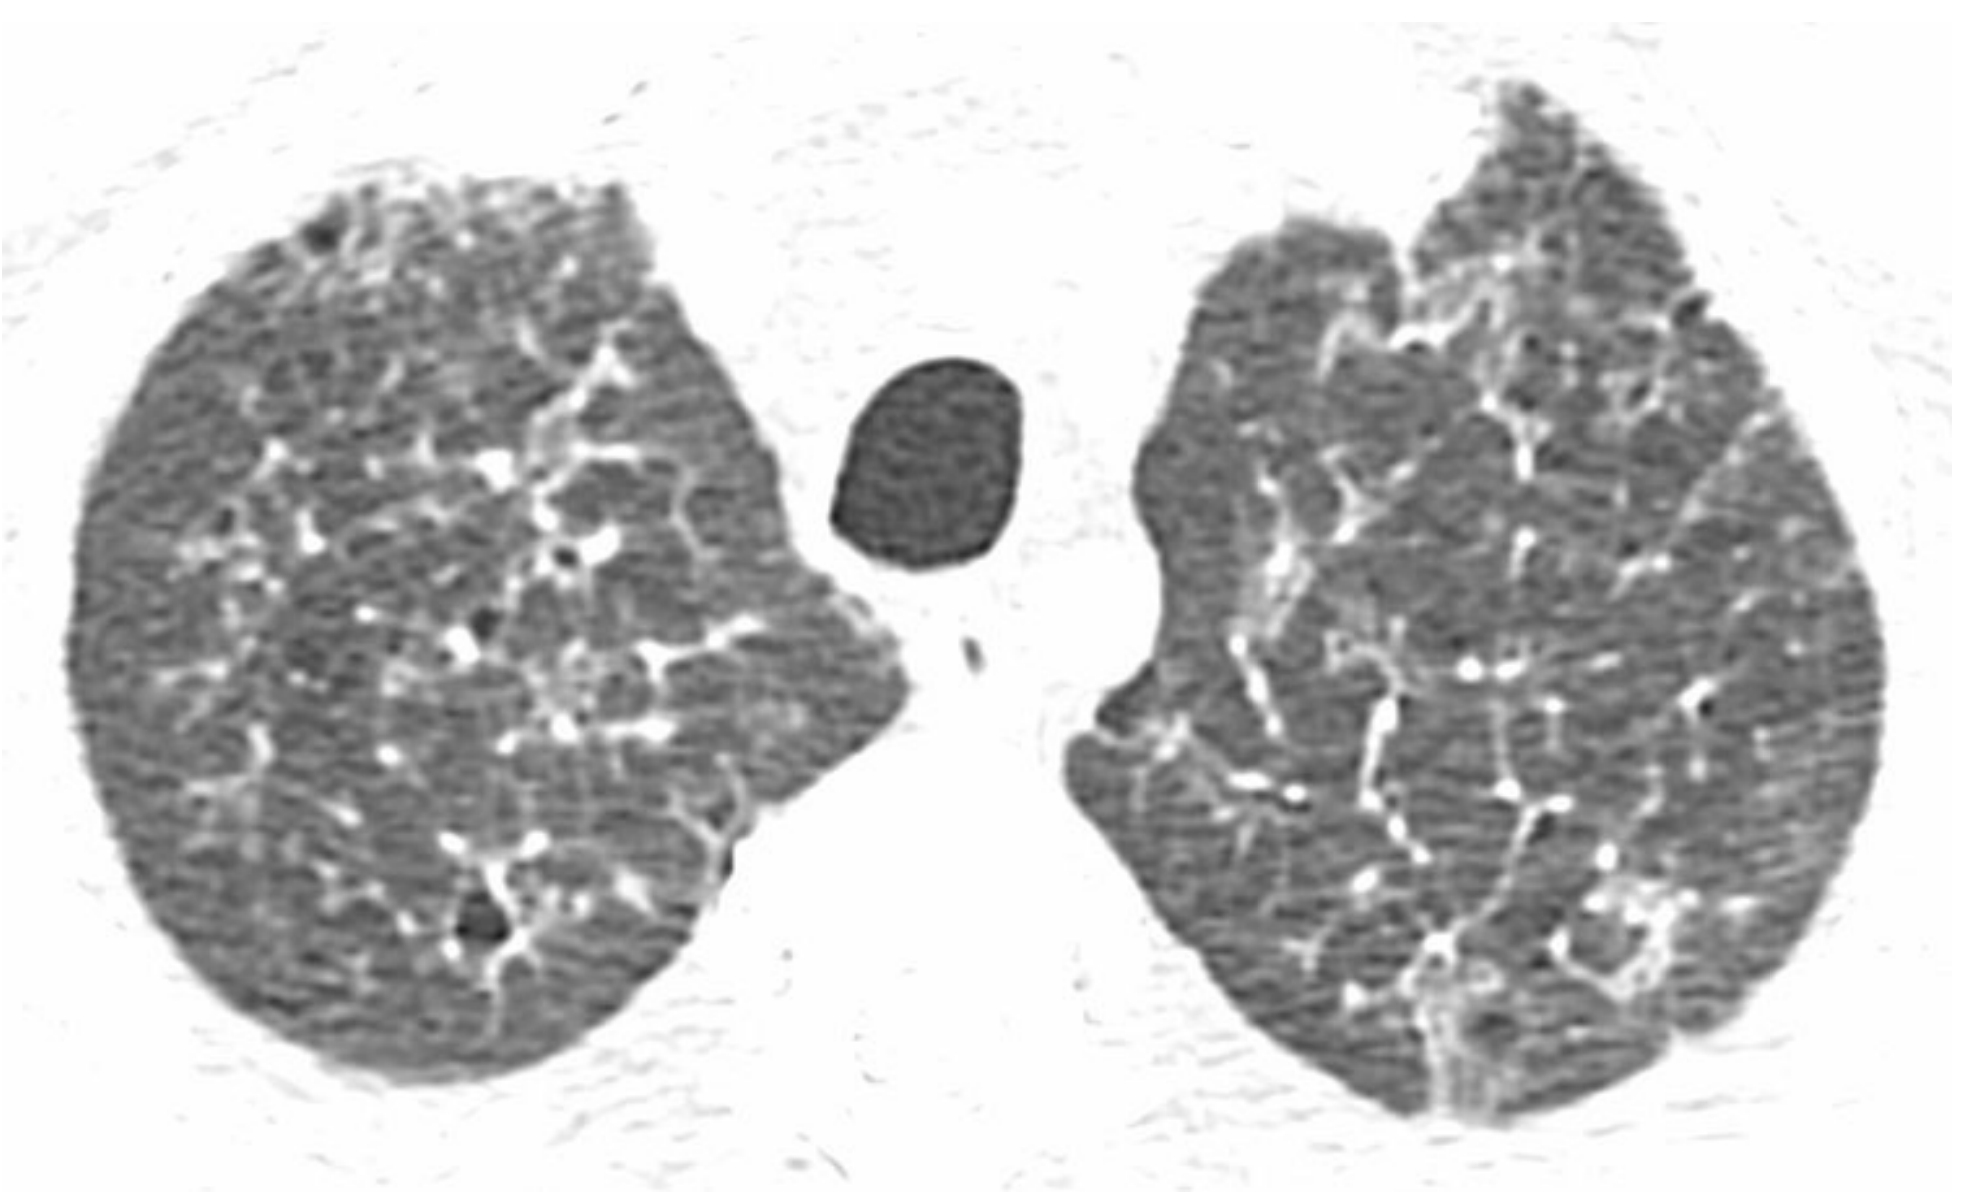

eb8e21eebff9ef7cc5bf91aa43df6ecf.png

炎症与纤维化的HRCT不同表现。

间质性肺炎表现为不同程度的炎症和纤维化;A和B. 2例结缔组织病患者的非特异性间质性肺炎。

A.HRCT显示GGO,无明显的纤维化征象,提示潜在可逆的炎症性病变;

B.HRCT显示牵拉性支气管扩张(箭)及不规则网状影的纤维化征象,提示对治疗不敏感的肺部瘢痕。